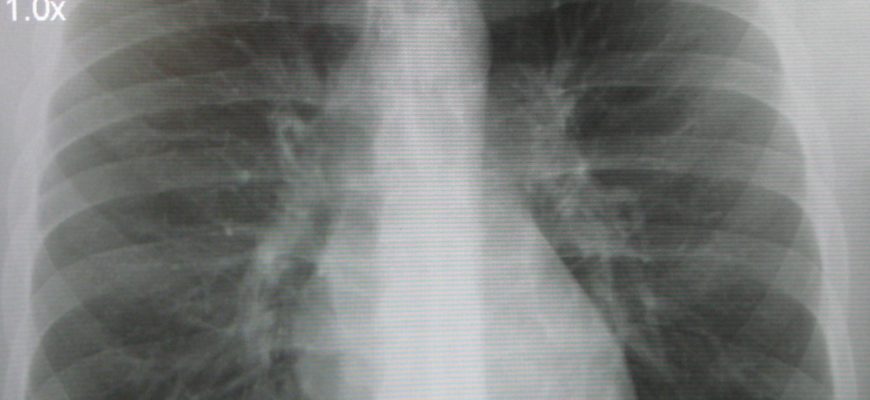

Обычно здоровый человек, у которого раньше не было заболеваний легких, у него есть нормальные FLG: чистые легочные поля без затемнения. В случае патологических изменений рекомендуются тесты: компьютерная томография, MSCT, МРТ.

Оценка флуорографии начинается с определения состояния изображения легких: усиленные или правильные, легочные корни: упорядоченные или рассеянные, плевральные пазухи: свободно или нет, средостенные тени. Повышенная легочная картина характерна для острого воспаления любого генезиса. Фиброз указывает на получение проникающих травм, хирургического вмешательства, туберкулеза, пневмонии. Фокусные тени в центральных и нижних долях указывают на очаговую пневмонию, в верхних долях для туберкулеза. Обнаруженные потомки указывают на изолированный кальцифицированный ниду более ранней инфекции, включая туберкулез или сифилис, черви, бактериальные атаки и не опасны.

Беспорядочные легочные корни предполагают воспаление или бронхит, ХОБЛ. Адгезии, слои на плеве — воспаление различной природы. Бесплатные отсеки или с экссудатом — важно для плевры. Расширенная тень средостения указывает на патологию сердца, но нет диагностической ценности. Движение металла указывает на накопление экссудата или воздуха в плеве, большие опухоли легких и требует срочной консультации с грудным хирургом.